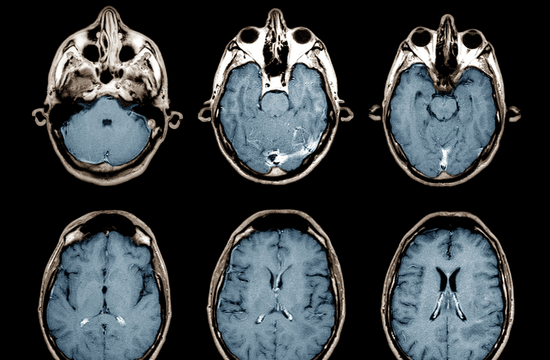

אזור הבטן מכיל כמה מהאיברים היותר חיוניים ורגישים בגופנו ובהם הלבלב, הכבד והמעי הדק. פתולוגיות שונות במבנה הרקמות של איברים אלה או נגעים בהם מחייבים בירור מעמיק ומדויק והבדיקה הטובה ביותר לשם כך היא האם.אר.איי (Magnetic Resonance Imaging).

בדיקת MRI בכבד

המצבים העיקריים המחייבים בדיקת MRI של הכבד הם: מעקב אחר חולי הפטיטיס B או הפטיטיס C שכן הם מתאפיינים ברמת סיכון גבוהה במיוחד להתפתחות גידולים ממאירים, וכן אנשים שלקו במחלת שחמת הכבד (שגם הם בקבוצת הסיכון הנ"ל).